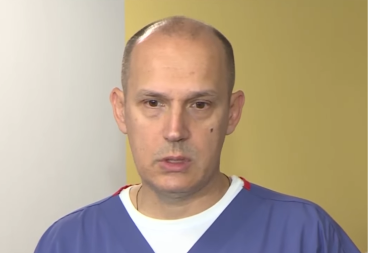

- Duboko smo zahvalni timu lekara na čelu sa prof. dr Dimitrijem Nikolićem koji nam je zaista pružio maksimalnu podršku kroz ceo proces. Od same procedure primanja terapije, monitoringa koji je usledio nakon, do toga što su i danas uz nas - rekla je Sonja.

Tip II je srednji oblik bolesti. Postoje tri terapije u svetu, a one su dostupne i u Srbiji. Ključno je da se bolest dijagnostikuje na vreme, i da se terapija primi u najkraćem mogućem roku jer to u najvećem broju slučajeva obezbeđuje tipičan rast i razvoj dece nadalje.